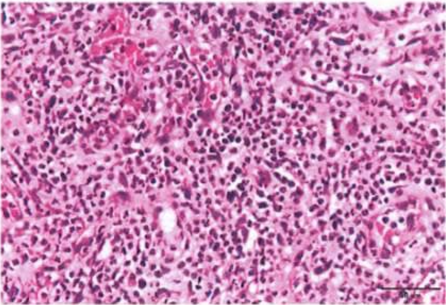

病理組織切片,確認鱗狀上皮癌細胞型態

經組織病理學診斷為鱗狀上皮細胞癌,術後接受免疫細胞治療數個月,待療程結束後三週,以癌識優® 檢測評估治療效果。